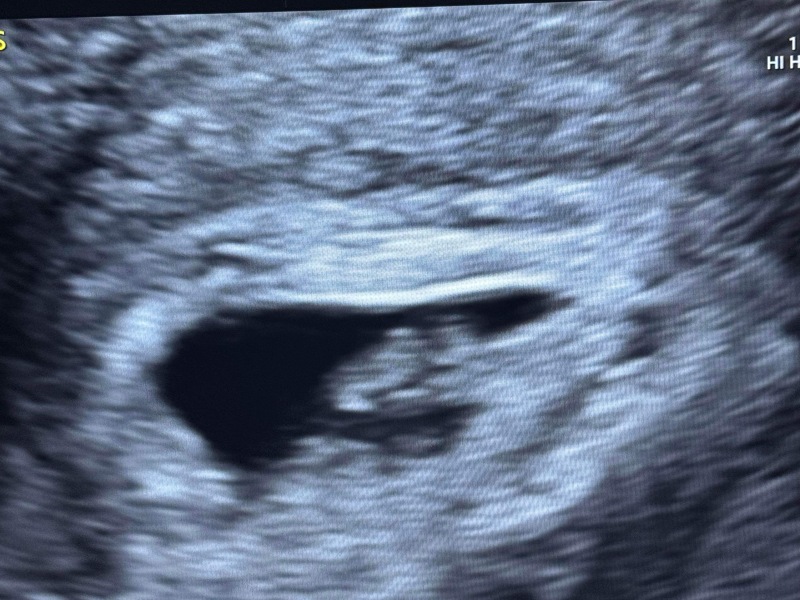

CluelessInLondon · 16/02/2024 10:59

I had my scan this morning - was really anxious beforehand and it was quite weird being back at the EGU (and being scanned by the same sonographer who had to tell me last time that my pregnancy was over), but everything is looking good. I'm 7+2 today and baby is measuring 7+1 with a nice heartbeat. It looks a bit like a potato but it's a healthy potato right now and that's all I really wanted! They're going to scan me again in two weeks' time on the same day as my booking appointment to check things are still looking okay, but right now it feels a little bit more real and I'm hoping I can relax just a bit.